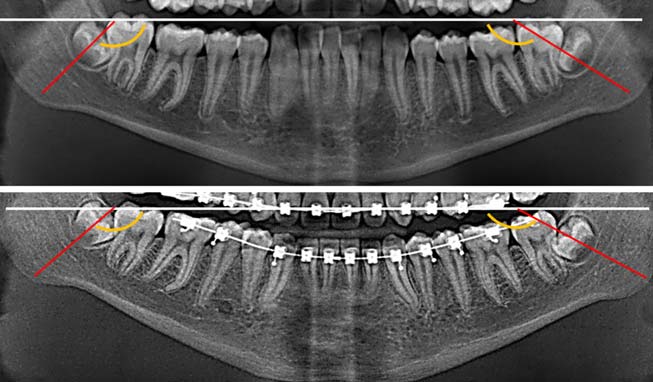

На ортопантомограмме направление прорезывания зачатков постоянных зубов было нарушено, выявлен недостаток места в дуге для прорезывания боковых резцов (рис. 2).

Рис. 2. Ортопантомограмма пациента Л., возраст 8 лет 6 мес

В возрасте 12 лет по причине задержки прорезывания постоянных зубов и неравномерной резорбции корней временных моляров [28] пациент был направлен на ортопантомографию и удаление временных зубов (рис. 3).

Рис. 3. Ортопантомограмма пациента Л. 12 лет

Кроме того, на ортопантомограмме выявили искривление корней постоянных зубов (рис. 7), что затрудняло их перемещение, а нормализация наклона корней при этом не представлялась возможной.

Рис. 7. Ортопантомограмма пациента Л. 15 лет

На ортопантомограмме после завершения ортодонтической коррекции окклюзии выявлены незначительная асимметрия положения зубов и искривление корней отдельных зубов (рис. 9).

Рис. 9. Ортопантомограмма пациента Л. 17 лет

Положение зачатков зубов 2.8, 3.8 и 4.8 в динамике наблюдения от 15 до 17 лет ухудшилось (рис. 10).

Рис. 10. Изменение наклона нижних третьих постоянных моляров пациента Л. относительно окклюзионной плоскости на ортопантомограммах в возрасте 15–17 лет

Это подтверждала динамика наклона осей постоянных зубов и зачатков третьих постоянных моляров относительно окклюзионной плоскости (табл. 3).